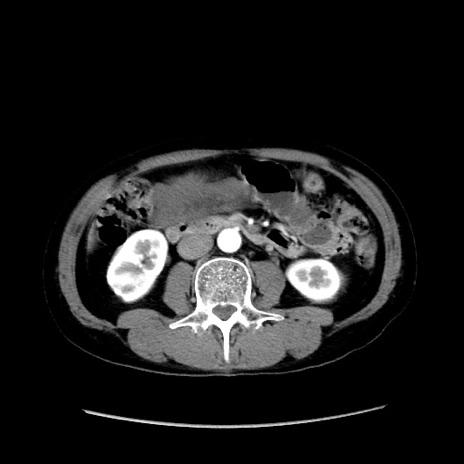

冠状断像

【症例】40歳代 男性

【主訴】腹痛

【現病歴】4時間ほど前に電車に乗車中に臍部上より腹痛出現。徐々に増悪し起立困難となり、救急外来受診。生ものは数日食べていない。今朝お雑煮を食べた。

【身体所見】BT 36.8℃、BP 117/84mmHg、HR 91/min、SpO2 97%、苦悶様、腹部:臍上部広範囲圧痛あり、反跳痛±

【データ】WBC 8100、CRP 0.03